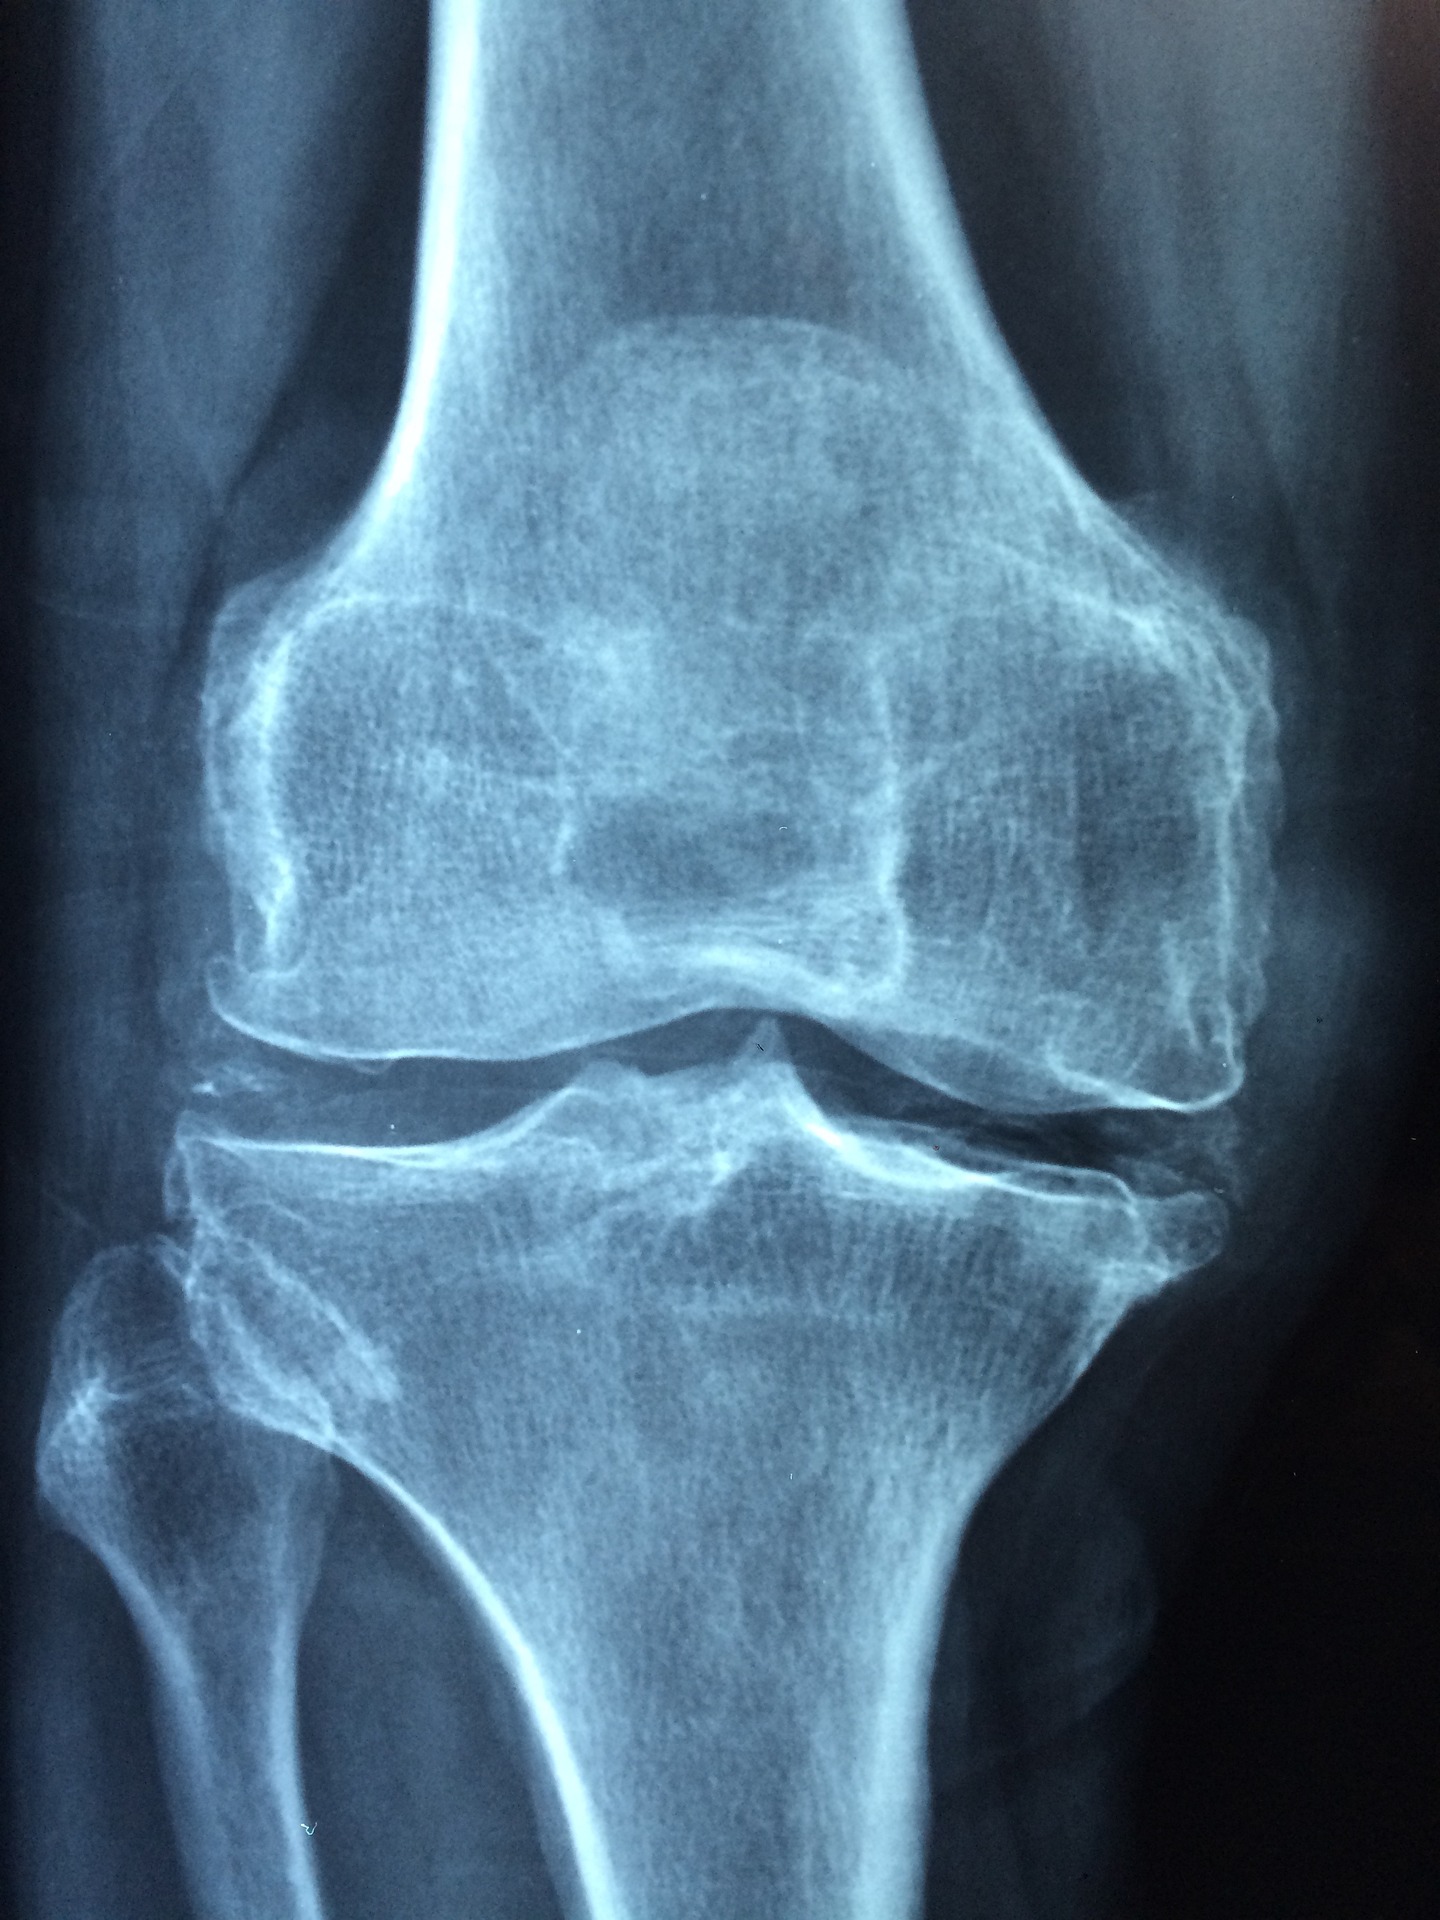

2. 관절염

대부분의 관절염 환자는 다리 또는 팔의 부위가 관절염에 가장 많이 호소합니다. 그러나 오른쪽 옆구리는 관절염이 있는 경우 아픈 경우가 생길 수 있습니다. 그 이유는 다음과 같습니다.

첫째, 오른쪽 옆구리는 다리보다는 가벼운 부위이기 때문에 오른쪽 옆구리의 관절이 스트레스를 받기 쉽게 됩니다. 관절염이 있는 경우 이러한 스트레스가 관절내에 쌓이게 되어 오른쪽 옆구리를 가려 아픔을 느낄 수 있게 됩니다.

둘째, 오른쪽 옆구리는 일상생활 중 운동을 잦게 하는 부위이기 때문에 관절염이 있는 경우 이 부위에 더 많은 스트레스를 줄 수 있기 때문에 오른쪽 옆구리가 아픈 경우가 발생합니다.

이 경우에도 바로 병원으로 가 의사와 상담해야합니다.

3. 허리디스크

허리디스크가 있는 경우 오른쪽 옆구리가 아픈이유에 대해서 알아보겠습니다.

대부분의 경우, 오른쪽 옆구리의 아픈 원인은 허리디스크에 의해 발생합니다. 허리디스크는 허리 관절과 뼈 사이의 연결부위, 즉 디스크가 상하로 압축되고 과다한 부하를 받아 탈락되는 것으로 이해되고 있습니다. 이는 외상성 손상 또는 척추관절의 노화에 의해 발생할 수도 있습니다. 허리디스크는 고령화가 진행됨에 따라 자주 발생하고, 일상생활에서 발생하는 많은 스트레스는 급성 허리디스크를 유발할 수 있습니다.

허리디스크가 약해지거나 탈락할 때, 그 주변의 뼈나 관절의 압박은 신경을 압박하거나 부실하게 만들 수 있으며, 이는 오른쪽 옆구리에 통증이나 불편감을 초래합니다. 또한, 허리디스크에 의해 신경이 압박되면 그 주변 근육이 긴장되고 근육해로 인한 추가 통증이 오른쪽 옆구리에 영향을 줄 수도 있습니다.

따라서, 오른쪽 옆구리가 아픈 경우 허리디스크가 원인일 수 있으므로 전문의 또는 의사와 상담하여 허리디스크 치료를 검토하는 것이 좋습니다. 정확한 진단을 받고 적절한 치료를 받기 위해 꼭 의료 전문가에게 상담해야 합니다.